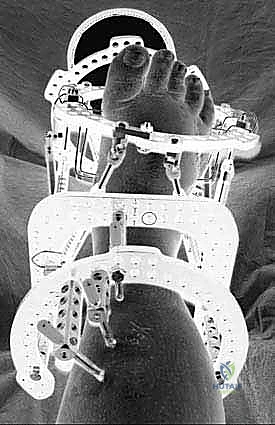

2. المرحلة الأولى: تطبيق جهاز التثبيت الخارجي (External Fixator Application)

- التدخل المحدود: بدلاً من شق القدم بالكامل، يتم عمل ثقوب صغيرة جداً (بضعة مليمترات) في الجلد.

- إدخال الأسلاك: يتم تمرير أسلاك معدنية رفيعة جداً وقوية (K-wires) ومسامير نصفية (Half-pins) عبر العظام في الساق والقدم بأماكن استراتيجية محددة مسبقاً بدقة لتجنب الأعصاب والأوعية الدموية، وذلك تحت توجيه الأشعة السينية المباشرة (C-arm) في غرفة العمليات.

- تجميع الإطار: يتم توصيل هذه الأسلاك بحلقات خارجية معدنية أو كربونية تحيط بالساق والقدم (إطار إليزاروف). يتم تثبيت هذه الحلقات معاً بواسطة دعامات قابلة للتعديل.